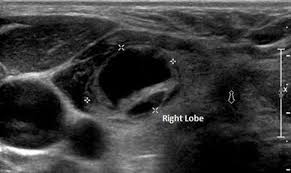

Idea Of Echographie de la thyroide PDF